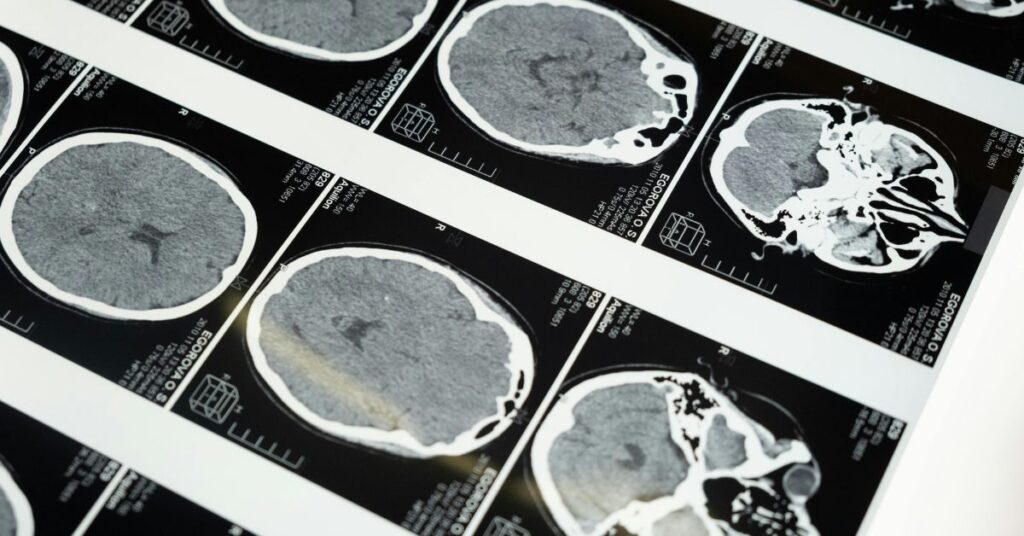

A combinação de suplementos contra tumor cerebral agressivo tem sido desenvolvida por um estudo conduzido na Índia que indica mudanças no comportamento do glioblastoma, considerado o tipo mais difícil de tratar. Nesse contexto, a equipe do Centro Avançado de Tratamento, Pesquisa e Educação em Câncer realizou a pesquisa e publicou os resultados na revista Nature em 30 de setembro de 2025. Assim, os cientistas apresentaram uma abordagem que evita o ataque direto às células do tumor.

Após a cirurgia, a equipe analisou em laboratório os tumores removidos. Nos pacientes que utilizaram os suplementos contra tumor cerebral agressivo, o marcador Ki-67, associado à multiplicação das células tumorais, apareceu cerca de um terço menor. Além disso, as análises indicaram queda aproximada de 41% em moléculas que permitem ao câncer escapar do sistema imune.